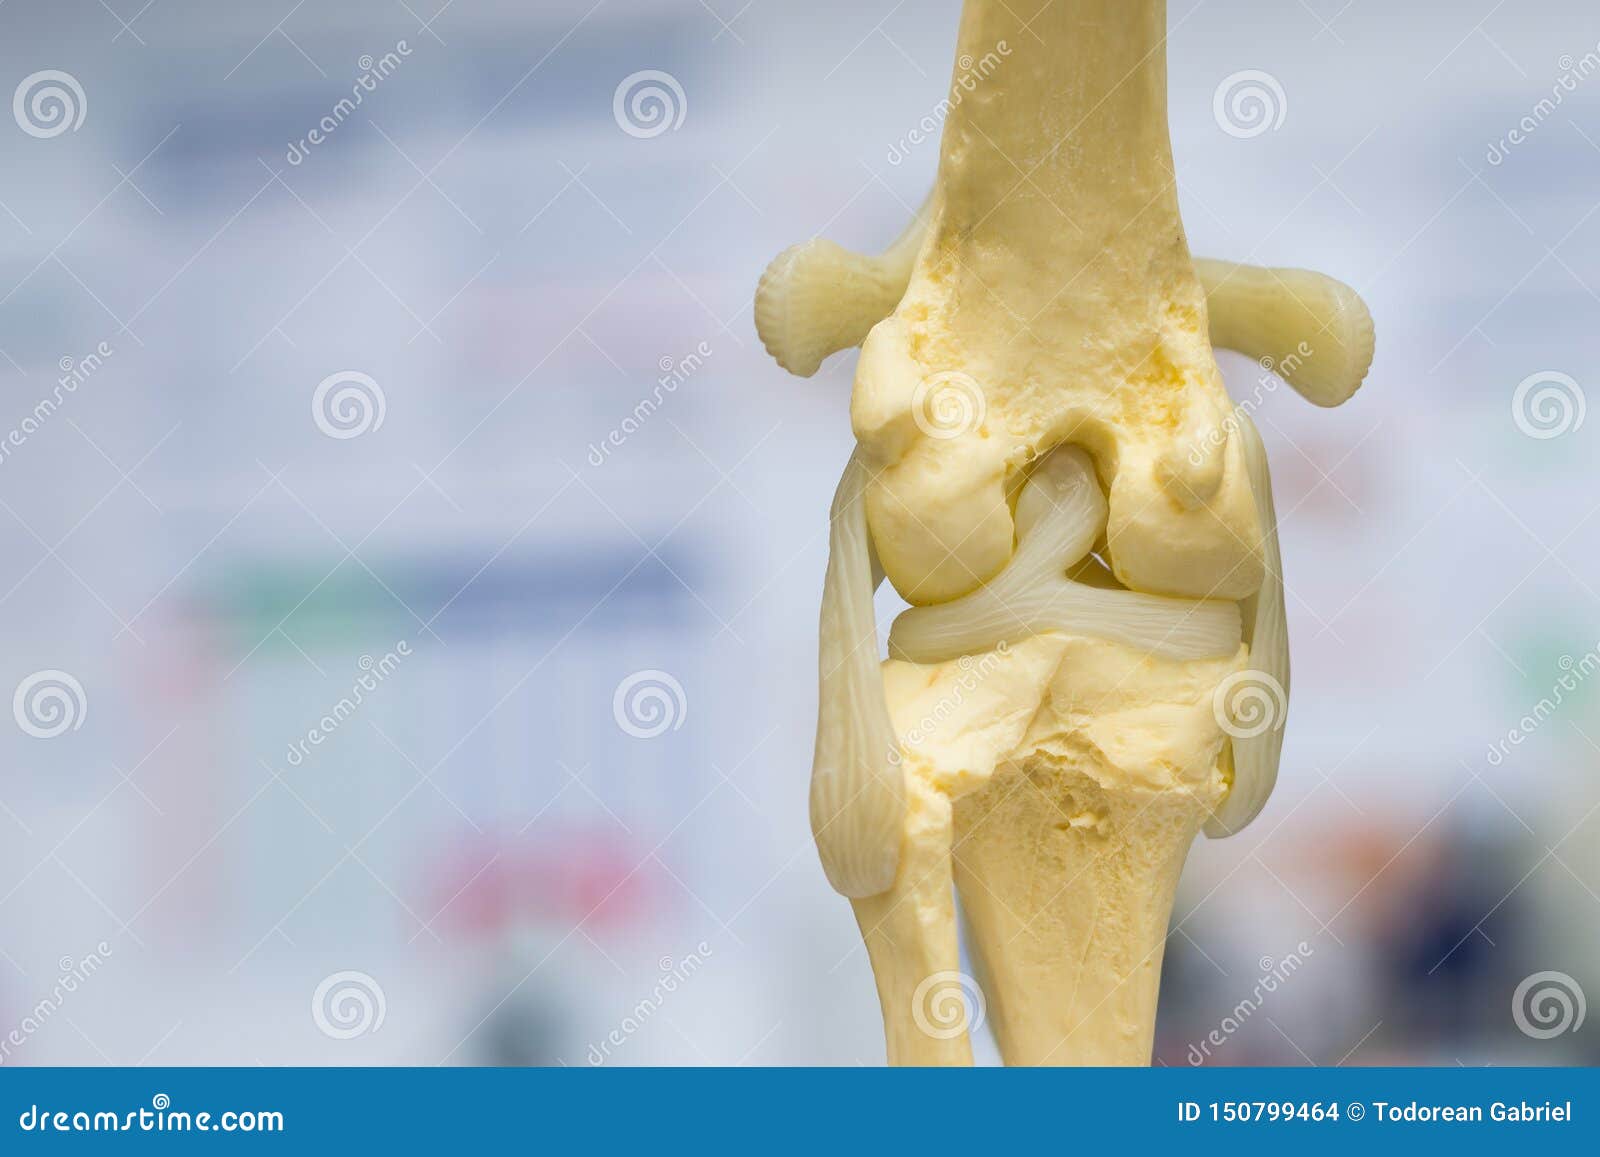

From www.dreamstime.com

Dog Knee Joint Mold Back View, Meniscus and Cruciate Ligament Stock Dog Knee Meniscus Tear Meniscal injuries on their own are uncommon in dogs, but the medial meniscus is very prone to tearing when the cranial cruciate ligament is ruptured. Limping is often the first sign of a cruciate problem. A dog’s knee, also referred to as a stifle, is a complex structure consisting of: The meniscus can also degenerate over time. Dogs and cats. Dog Knee Meniscus Tear.

From www.alamy.com

dog knee joint mold back view, meniscus and cruciate ligament Stock Dog Knee Meniscus Tear The meniscus can also degenerate over time. Dogs and cats with meniscal tears are typically presented with chronic or acute pelvic limb lameness that is often only partially alleviated with conservative management. The most common type of tear is the. In humans, a meniscal tear is a common sports injury, usually triggered by twisting the knee. Meniscal injuries on their. Dog Knee Meniscus Tear.